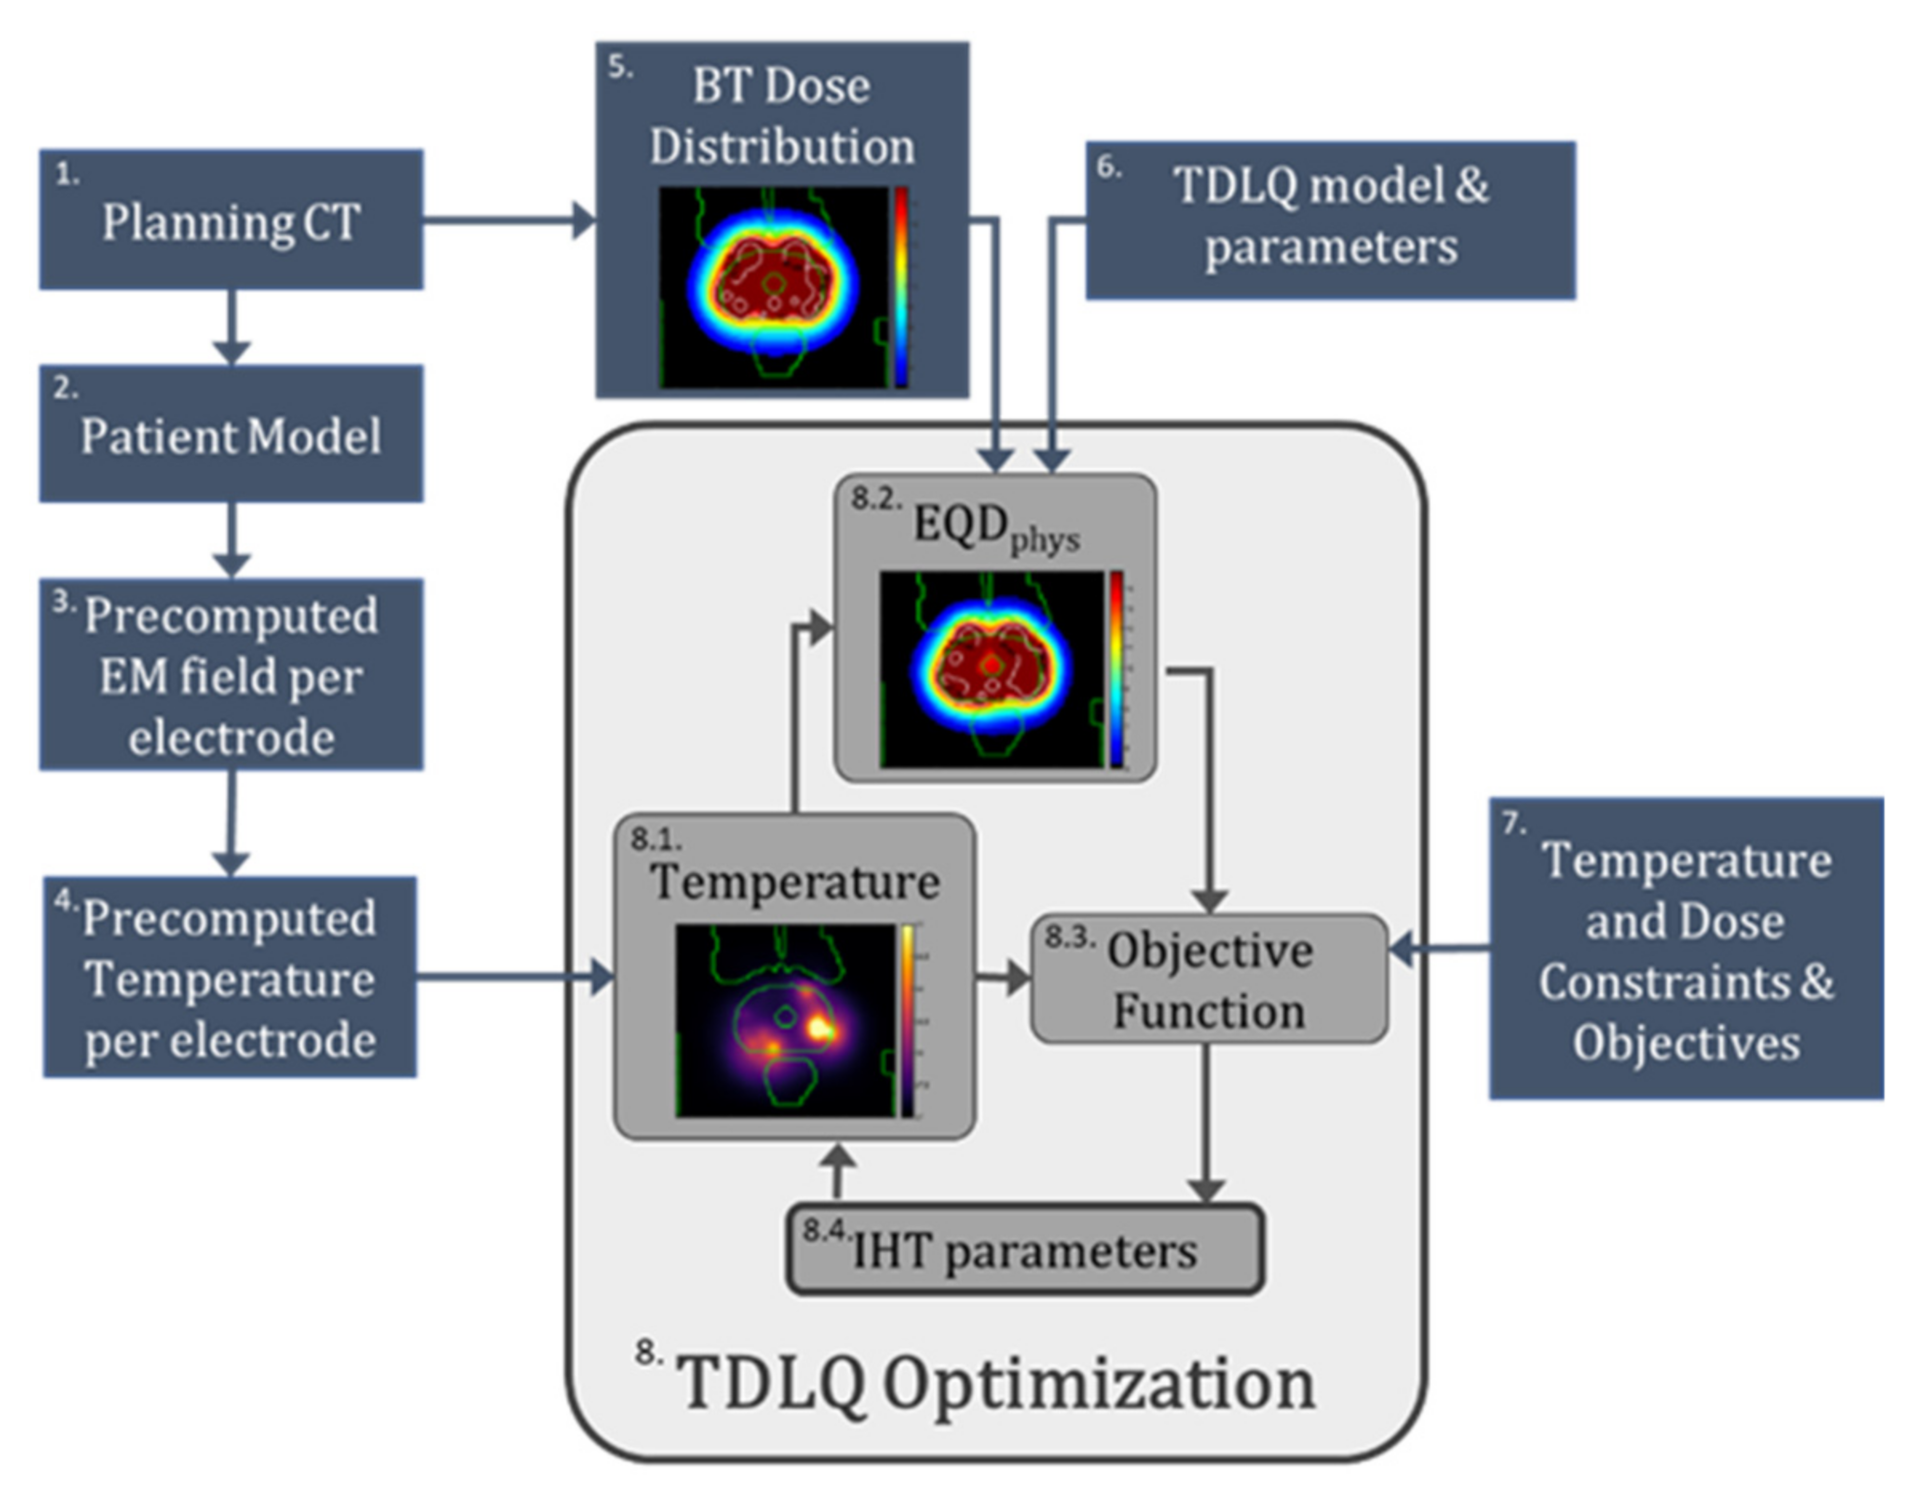

2.1. Overview of Optimization Framework

2.2. Patient Anatomy Modeling

2.3. TBT Applicator Modeling, Positioning, and E-Field Calculation

2.4. Temperature Calculation and Superpositioning

2.5. HDR-BT Treatment Plan and Dose Calculation

2.6. Thermoradiobiological Modeling

2.7. Thermoradiobiological Objective Function and Optimization Algorithm